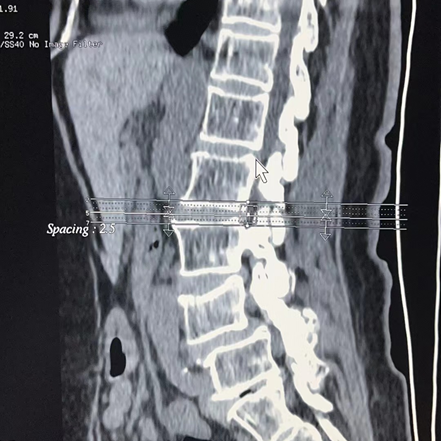

患者王婆婆已經(jīng)71歲了,近13年來反復(fù)腰部伴雙下肢疼痛無力,保守治療無效,近期尤為明顯,行走幾百米就小腿脹痛明顯,無法繼續(xù)走路,嚴(yán)重影響日常生活。加之子女遠(yuǎn)在國外,無法照顧王婆婆,她輾轉(zhuǎn)多個(gè)三甲醫(yī)院,最后選擇轄區(qū)較近的我院外科入住。入院后外科積極進(jìn)行圍手術(shù)期管理,醫(yī)患溝通,嚴(yán)格落實(shí)核心制度。完善相關(guān)檢查,診斷為腰4椎體骨折并滑脫、椎管狹窄。外科結(jié)合術(shù)前的各項(xiàng)檢查,細(xì)致的術(shù)前討論,制定了合理的手術(shù)方案,最終決定為患者實(shí)施“腰3-5置入椎弓根螺釘,腰4-5椎板切除減壓椎間植骨融合復(fù)位釘棒內(nèi)固定術(shù)”,歷經(jīng)3小時(shí),手術(shù)順利完成,術(shù)中出血僅300ml,,術(shù)后患者雙下肢感覺運(yùn)動(dòng)正常,腰腿疼痛立即緩解?;颊邔?duì)治療效果非常滿意。術(shù)后第3天已經(jīng)下床行走,春節(jié)前即將順利出院,過一個(gè)真正快樂、毫無病痛的春節(jié)!

腰椎后路滑脫椎管減壓植骨融合內(nèi)固定術(shù)是脊柱外科常用的手術(shù)方式之一,其手術(shù)方法主要是經(jīng)腰椎后路打開椎管,松解粘連、緊張的神經(jīng)組織,切除病變突出的腰椎間盤,并植入椎間融合器及內(nèi)固定裝置,從而達(dá)到解除神經(jīng)壓迫,緩解腰椎間盤壓力,重建脊柱穩(wěn)定,降低患者復(fù)發(fā)率的目的。適用于腰椎間盤突出癥導(dǎo)致的腰腿部麻木、疼痛等不適,或腰椎間盤突出癥病情反復(fù)發(fā)作或者久治不愈,以及存在腰椎節(jié)段性不穩(wěn)導(dǎo)致的腰椎滑脫、腰椎管狹窄癥、脊柱側(cè)彎畸形、馬尾神經(jīng)疼痛等腰椎疾病。